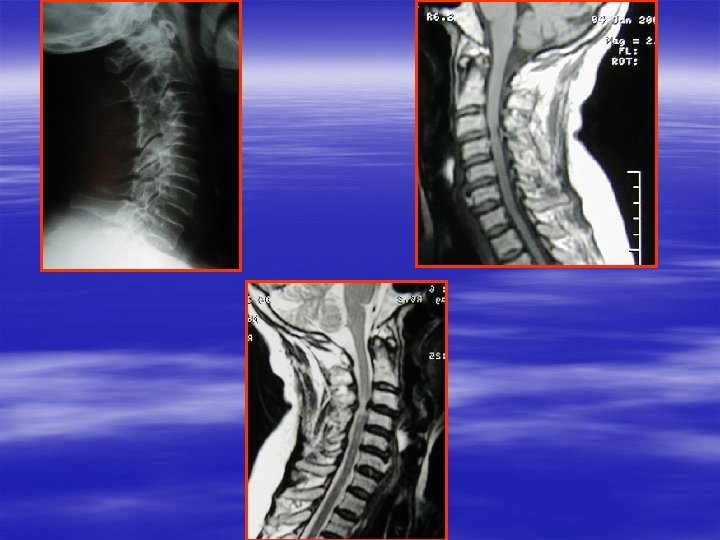

RADIO STANDARD Profil § § § Incidence fondamentale +++ Technique rigoureuse : occiput C 7 -T 1 Origine constitionnelle ou acquise de la sténose du canal rachidien § Incidences dynamiques : – Extension – flexion instabilité +++

RADIO STANDARD PROFIL : RESULTAT § Statique rachidienne : cyphose +++ § Sténose constitutionnelle : diamètre A-P : C 1 : 18 mm, C 2 : 16 mm, C 3 C 4 C 5 C 6 : 13 mm, C 7 : 14 mm – Hypoplasie avec transversalisation des lames +++ – Transversalisation et raccourcissement pédiculaire avec avancée des massifs articulaires – Hypertrophie constitutionnelle des corps vertébraux

IRM § § § Examen clé Inconvénient: statique Étude contenant et contenu Contrôle post-opératoire Dynamique : extension ++ Anomalies de signal de la moelle !! T 1, T 2 possibilité d’amélioration après chirurgie

§ Étude des structures ligamentaires postérieures : ligament jaune +++ § T 1 : Moelle + disque + § T 2 : – Diam A-P du canal risque de surestimation – Moelle +++ – Modic cervical ? – Ligament § Contrôle post-op